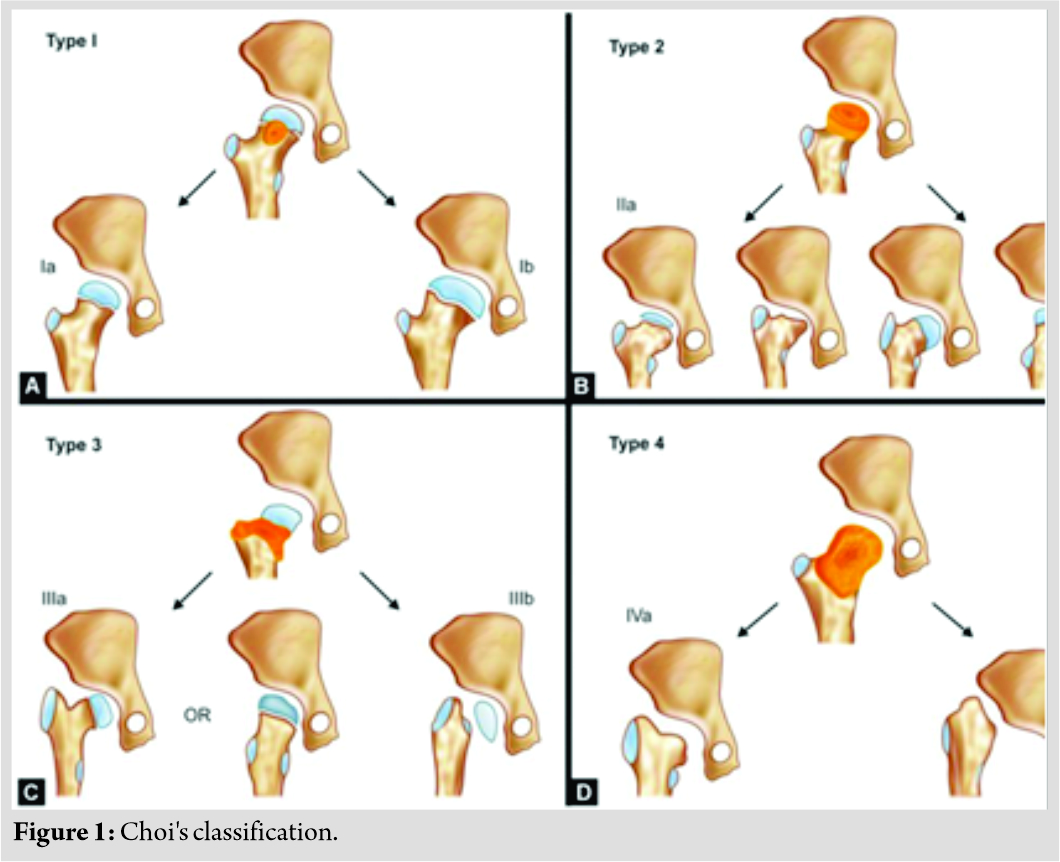

Acute septic arthritis of the hip in children requires prompt diagnosis and treatment. However, this may not be possible, because of missed diagnosis at an early stage of the disease. This is especially true in the setting of developing countries like India where access to specialist pediatric orthopedic care is extremely limited. The resulting sequelae of septic arthritis are diverse and may include minimal residual deformity, coxa breva with deformed head, or coxa vara or valga due to asymmetrical physeal closure, or complete destruction of femoral head and neck with no articulation at hip joint [1, 2, 3]. Choi’s radiographic classification is the most commonly used classification for this condition (Table 1 and Fig. 1) [4].

Varieties of procedures have been described in the orthopedic literature for various stages of disease and range from simple observation to complex procedures such as limb lengthening and Ilizarov hip reconstruction (IHR) [2]. The common goal of treatment of all these procedures is to achieve a mobile, stable, pain-free hip joint with minimal limp and limb length inequality. The problem in Choi’s Type 2 hip is femoral shortening due to premature physeal closure and abductor dysfunction due to coxa vara. We report here two cases of this type treated with a simple operation of distal trochanteric advancement and equalization of limb length by monorail external fixator.

Case Report: We present two cases of Choi’s Type 2 septic hip sequelae, a 14-year-old female and a 13-year-old male, both had painless limp and limb length discrepancy managed by greater trochanteric advancement with limb lengthening by monorail external fixator at single sitting.